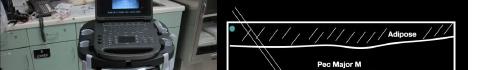

Prior to the start of the procedure, the patient must have IV access and be placed on a cardiac monitor. After informed consent has been obtained, the patient is positioned in the supine position with the head to the contralateral side of the proposed block. The physician stands at the head of the bed above the ipsilateral breast with the ultrasound screen in direct line of sight (commonly at the level of the contralateral hip). The ultrasound probe is initially placed in the sagittal plane at the midclavicular line until the clavicle, pectoralis muscles, and axillary artery and vein are visualized. The transducer is then translated caudally until the third and fourth intercostal spaces are visualized (Image 1).

At this point, the pectoralis major and minor muscles can be visualized. By rotating the transducer 45 degrees clockwise, the thoracoacromial artery can be identified between the pectoralis major and minor muscles. Also, the serratus anterior muscle should be identified resting just above the anechoic rib (Image 2).

Image 1. Initial probe placement for the pectoralis nerve block I and II illustrated on a model: the blue line indicates transducer, and the green dot indicates directional marker corresponding to ultrasound image. Image 2. Final probe placement prior to the pectoralis nerve block I and II: blue line indicates transducer, and green dot indicates directional marker corresponding to ultrasound image.